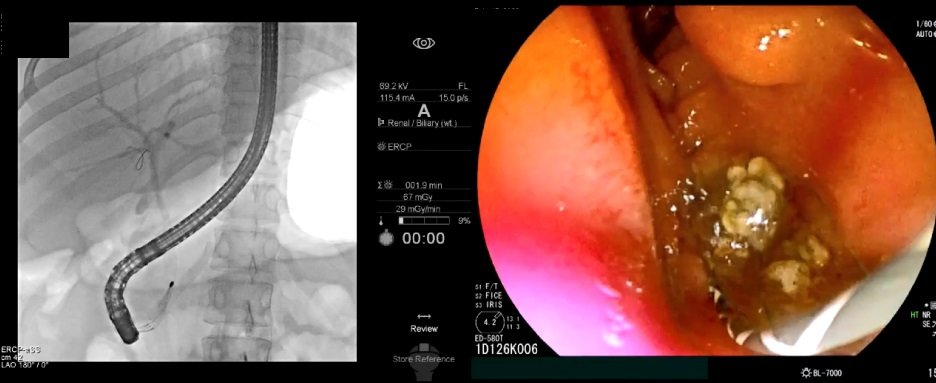

초음파내시경으로 담관결석이 관찰되면 내시경적 역행성 담췌관조영술(ERCP)을 통해 담관결석을 제거한다. ERCP는 담석의 정확한 위치를 확인하기 위한 특수내시경과 방사선을 이용한 시술이다. ERCP로 담관결석을 제거한 뒤에도 재발을 막기 위해 담낭담석을 제거하는 담낭절제술이 필요하다.